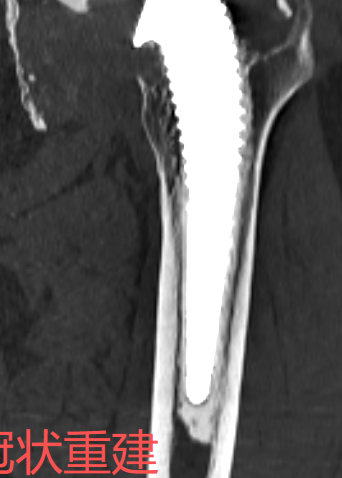

对比图像清晰显示:3月11日常规平扫图像中,金属伪影严重,结构显示不清;而3月12日采用MAR技术扫描后,无论是横断面还是冠状位重建图像,金属伪影均基本消除,解剖结构清晰可见,为临床精准评估和假体设计提供了可靠依据。

注:以下图片展示了常规平扫与MAR技术扫描的对比效果,清晰呈现金属伪影消除技术的临床价值。

MAR技术扫描(金属伪影基本消除)

MAR技术冠状重建 (金属伪影基本消除)